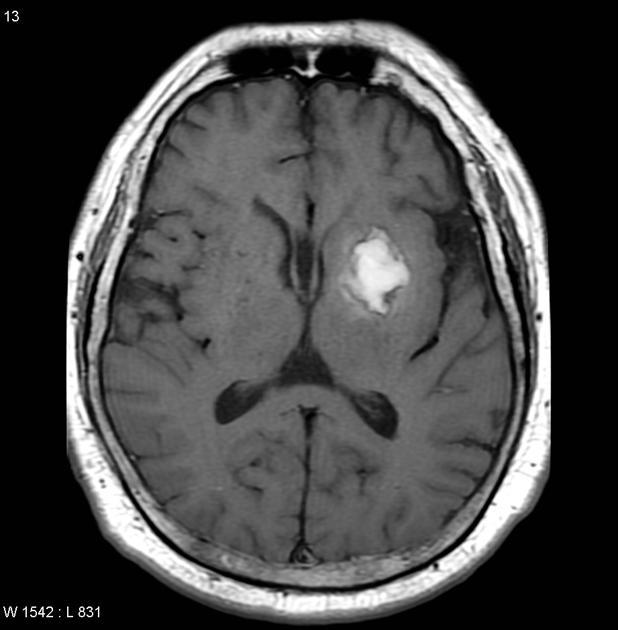

2. MRI- MAGNETIC RESONANCE IMAGING

1. Determines extent of brain injury (Lewis et al, 2014).

2. CT: COMPUTED TOMOGRAPHY

1. Indicates the size and location of the lesion and helps to quickly identify the type of stroke (Lewis et al, 2014).

1. CT or MRI needed BEFORE administering tPA

1. Patients eligible for tPA should have CT scan within 25 mins of admittance. (Summers, Leonard, Wentworth, Saver, Simpson, Spilker, Hock, Miller, Mitchell, 2009)